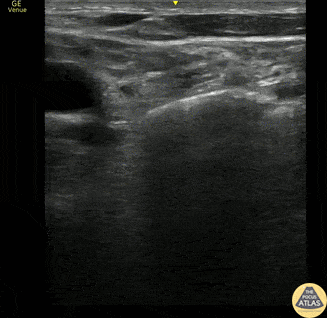

Soft Tissue - Supraclavicular Lymphadenopathy

This is a 60s y.o. gentleman w/ PMHx remote axillary abscess who was found to have a nontender supraclavicular mass. When scanning medial to lateral in the supraclavicular fossa, the mass is revealed to be a ~3x4cm lymph node. The wedge shaped hypoechoic structure seen represents the hilum, and color doppler reveals organized blood flow. Peripheral hypoechoic regions may represent necrosis. These findings are suspicious for malignancy vs reactive lymphadenopathy. Dr. Geoff Hogan Denver Health Residency in Emergency Medicine